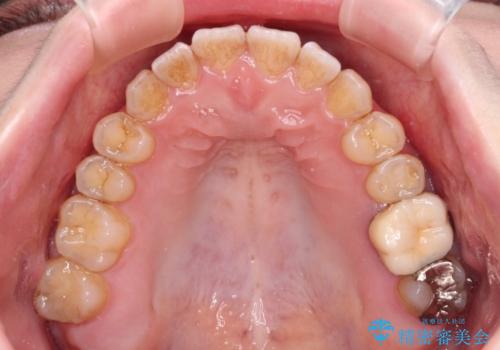

オープンバイトと前歯のデコボコをインビザライン矯正で解消

- 前歯の開咬を気にして来院された患者様です。

開咬の治療は、前歯を閉じるように動かすとともに、上下臼歯を圧下(骨内にめり込ませる)させることで進めて行きます。

インビザラインは臼歯の圧下を効果的に行えるため、インビザラインを用いて矯正治療を行うこととしました。